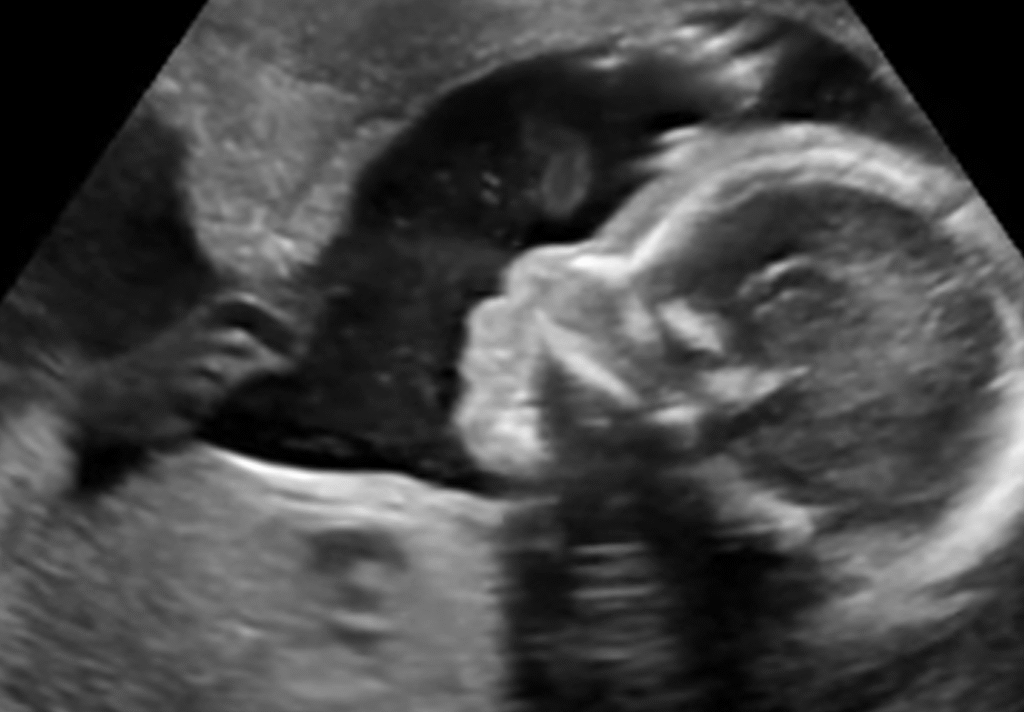

An anomaly scan during pregnancy is a detailed ultrasound that evaluates fetal development. It identifies structural abnormalities, growth issues, and organ formation. This scan helps detect congenital conditions early. It is typically performed between 18 and 22 weeks of gestation. Doctors recommend it especially for women with high-risk pregnancies or previous complications.

An ultrasound scan during pregnancy is non-invasive and painless. The patient lies on a couch while a technician applies gel to the abdomen. A probe captures high-resolution images of the fetus. The scan usually takes 20–45 minutes, depending on fetal position and clarity. Advanced equipment allows 3D and 4D imaging for more precise evaluation.